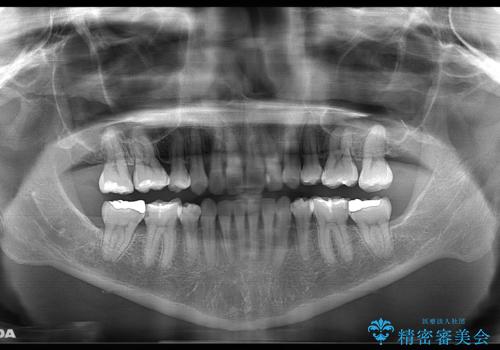

口元の突出感の改善や歯の移動量などを考慮し、抜歯を伴うワイヤー矯正での治療を選択しました。

抜歯を行うことで前歯を後ろへ下げるスペースを獲得し、口元の突出感や歯のガタつきを改善していきました。